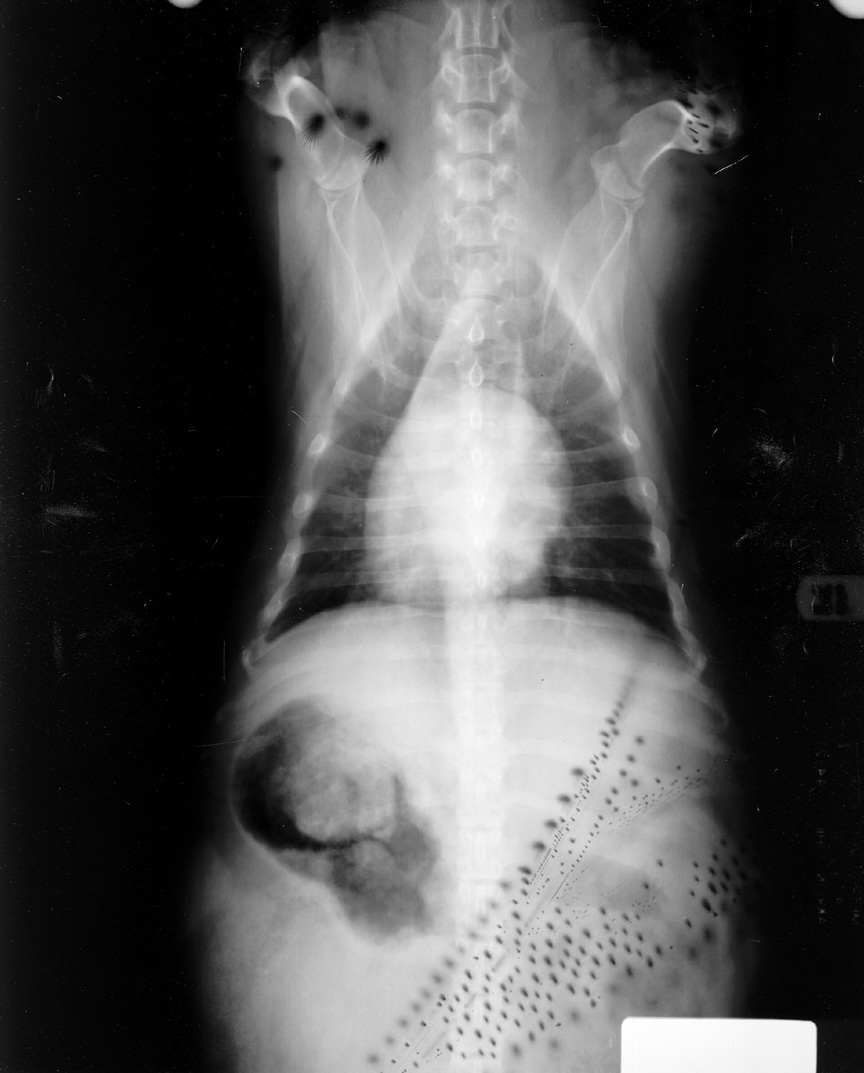

Static

Static causes black branching artifact on the film due to exposure of the film to the elecrical spark of the static discharge.